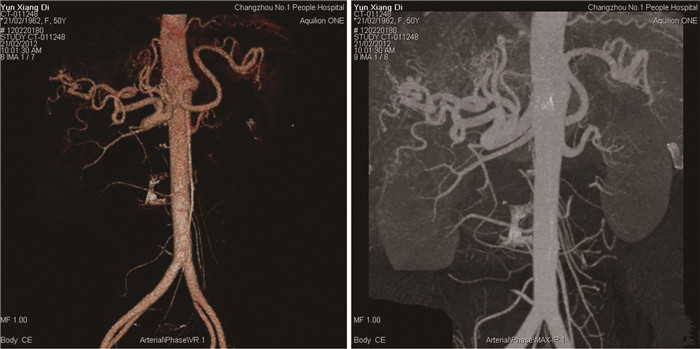

Hereditary hemorrhagic telangiectasia of the liver: A case report

Tingting WANG, Liang MA, Jianping CHEN

2022, 38(2): 423-425. DOI: 10.3969/j.issn.1001-5256.2022.02.032

Abstract(1009) HTML (348) PDF (2696KB)(39)

Abstract: